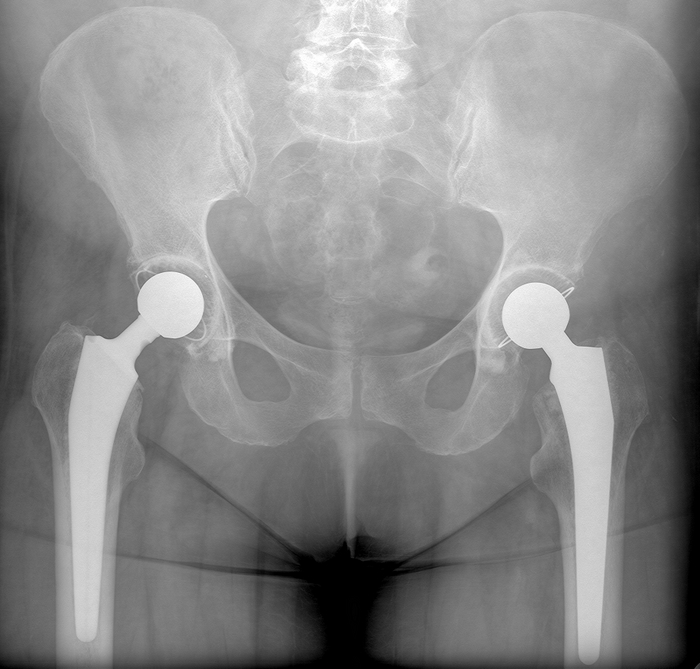

Планово для МСЭ обследовали мужчину, которому в 1983 г. в пьяной драке выстрелили из ружья в левое плечо. Плечевая кость была сломана выстрелом, перебеты все нервы (до сих пор не двигаются пальцы на руке, плохо гнется рука в плечевом суставе. Сформировался лодный сустав (т.е. кость не срослась вообще). Кость деформировна. В проекции перелома множественные металлические осколки дроби.